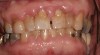

Drug-induced gingival enlargement is typically described as nodular, firm in consistency, and hard upon palpation. Clinical manifestations can be more severe in areas where local irritants such as plaque, defective restorations, and orthodontic or prosthetic appliances are present (Figure 1).7 Drug-induced gingival overgrowth is quite different between animals and humans. As demonstrated in rat models, the incidence of macroscopic gingival changes is usually close to 100% in all three of the previously mentioned classes of medication.8 In humans, however, the incidence has been reported to vary according to medication: 10% to 50% for phenytoin, 8% to 70% for cyclosporin-A, and 0.5% to 83% for nifedipine.6

Fig 1. A 66-year-old male patient with multiple restorations, taking 100 mg Dilantin (phenytoin) daily for approximately 5 years. (photo courtesy of Asim Alsuwaiyan, BDS)

Figure 1